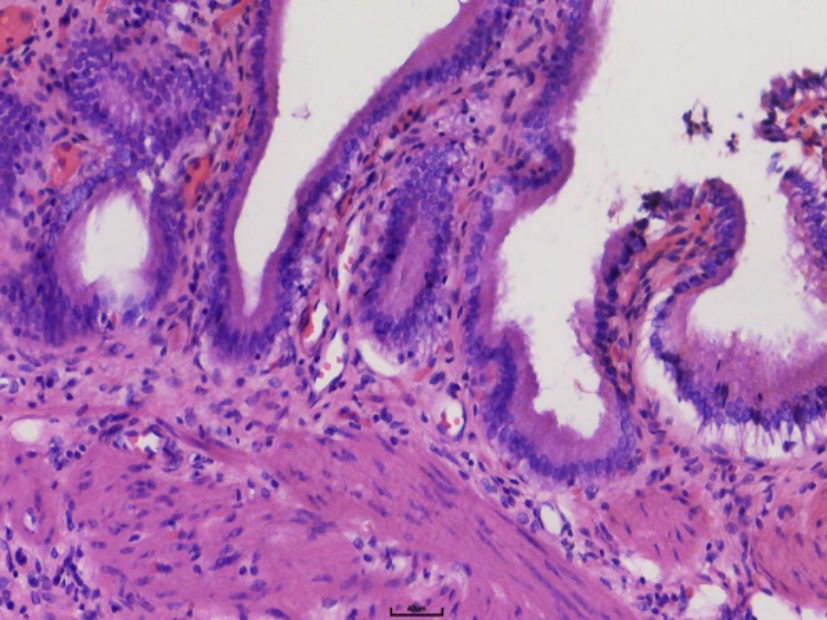

本研究共纳入9例HS患者,其中外科治疗7例,内科治疗2例。患者均为本中心连续收治病例。年龄中位数为30岁(8~64岁),其中成年人5例、青少年4例;男性6例、女性3例。共有4例患者具有明确家族遗传史。所有患者入院时均表现为皮肤巩膜黄染、脾肿大及不同程度的贫血。其中轻度贫血2例,中度贫血5例,重度贫血2例;2例患者合并腹痛症状(详见表1)。全部患者均接受骨髓穿刺活检,结果显示骨髓增生活跃,红系显著增生(图1),提示溶血性贫血特征。共4例患者完成基因检测,突变基因包括SLC4A1、ANK1、SPTB,其中以SPTB突变最为常见(2例) (图2)。影像学检查显示所有患者均存在不同程度的脾肿大(图3)。合并症方面:外科治疗组中6例患者伴胆囊结石,其中5例为单纯胆囊结石,另1例合并胆总管结石。1例合并乙肝肝硬化;内科治疗组中1例患者伴EB病毒感染。患者总体住院时间中位数为13天(8~35天)。外科组住院时间中位数13天(8~35天),内科组住院时间中位数12天(10~14天)。外科患者术后病理结果显示脾脏显著淤血、红髓减少并萎缩(图4),胆囊标本中5例存在慢性胆囊炎伴胆囊结石(图5)。

Figure 5. Gallbladder histopathology showing chronic cholecystitis (HE 200X)

5. 胆囊病理切片显示慢性胆囊炎(HE 200X)

肠梗阻(保守治疗后恢复),2例轻度胰漏及脾静脉血栓。出院时,总胆红素与间接胆红素较术前显著下降(p = 0.016);血红蛋白与红细胞计数虽有升高趋势,但差异无统计学意义(p > 0.05)。其中血红蛋白升高6例、下降1例;红细胞计数升高5例、下降2例。外科治疗可显著改善溶血状态和黄疸症状,但短期内血红蛋白改善幅度有限。